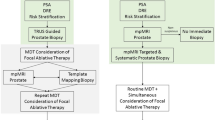

The current biopsy pathway is being re-defined with a shift towards MRI-targeted biopsy. 3D histopathological models reconstructed from TPM biopsies were used to show that a single biopsy needle targeted to the maximum lesion diameter on mp-MRI leads to the correct Gleason grade in nearly all cases [21]. There is evidence from recent randomised controlled trials which confirm that a pre-biopsy MRI with or without targeted biopsy is superior to standard TRUS biopsy [22]. Although MRI-US-targeted biopsy may enhanced detection of clinically significant disease, the effect on estimation of tumour volume remains under investigation.